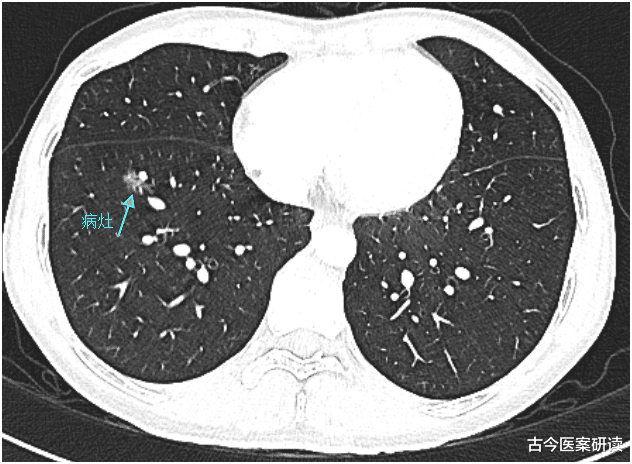

伴随着人们生活水平的不断提高 , 医疗的相关设备也不断完善 , 也因此大大提高了对疾病的诊断效率 。 人们对自身的健康意识也愈发重视了起来 , 不少人都会定期到医院体检 , 看看身体有什么症状 , 或者需要补充什么 。 假如确诊了疾病 , 如肺结节 , 千万不要着急 , 一定要想想平时乱吃了什么食物 , 会是下列4种吗?